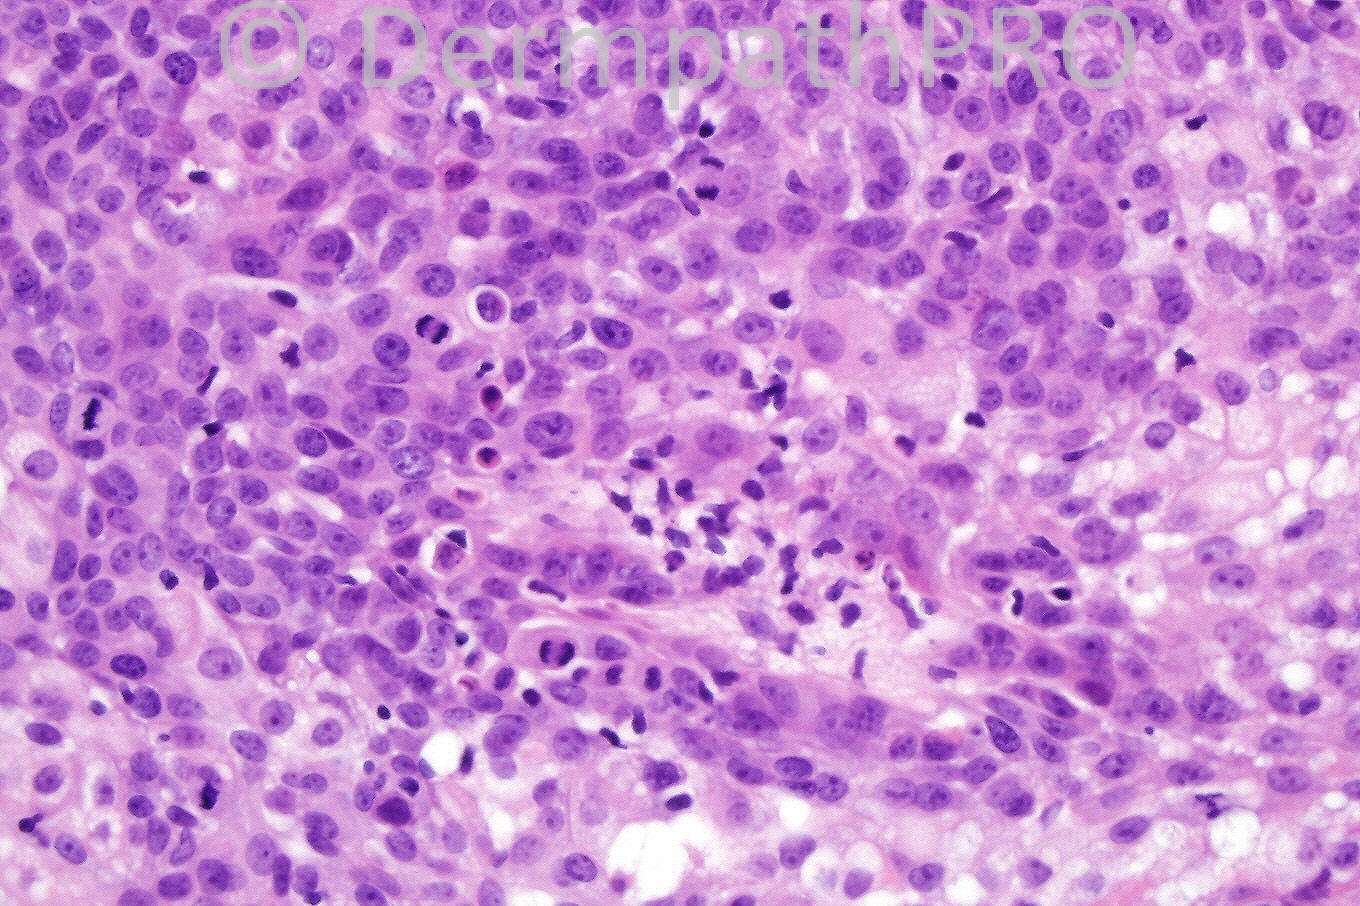

Female 82 years, papule on cheek.

The correct diagnosis is sebaceous adenoma. In the latter condition, the architecture of the sebaceous gland is maintained with basaloid cells at the periphery and sebocytes in the center. Rarely, sebaceous adenoma is much larger and may be mitotically active. This should not be misdiagnosed as sebaceous carcinoma. In sebaceoma, the sebaceous architecture is lost, the tumor is multinodular, has a fibrous stroma and cysts are common.

I can see multivacuolated cytoplasmic clear cell changes &cellular atypia in fig 4 so my impression is extraocular sebaceous carcinoma.

I will favor sebaceous adenoma as the lesion is made of sharply circumscribed lobules separ aged by compressed connective tissue. The architecture also is typical with the lesion connected and openingthat surface. The mature sebocytes are well centered in each lobule. The clefts that separate the tumor from the surrounding normal dermis are beautifully proofing the benign nature. The bubbly appearance of the sebocytes is fantastic !!!!!!! I would search for GIT carcinoma here to exclude Muir Torre Syndrome.